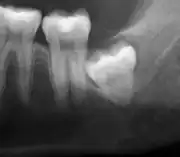

If the tooth cannot be assessed with clinical exam alone, the diagnosis is made using either a panoramic radiograph or cone-beam CT. Where unerupted wisdom teeth still have eruption potential several predictors are used to determine the chance of the teeth becoming impacted. The ratio of space between the tooth crown length and the amount of space available, the angle of the teeth compared to the other teeth are the two most commonly used predictors, with the space ratio being the most accurate. Despite the capacity for movement into early adulthood, the likelihood that the tooth will become impacted can be predicted when the ratio of space available to the length of the crown of the tooth is under 1.[5]: 141

Impacted wisdom teeth are classified by their direction of impaction, their depth compared to the biting surface of adjacent teeth and the amount of the tooth's crown that extends through gum tissue or bone. Impacted wisdom teeth can also be classified by the presence or absence of symptoms and disease. Screening for the presence of wisdom teeth often begins in late adolescence when a partially developed tooth may become impacted. Screening commonly includes a clinical examination as well as x-rays such as panoramic radiographs.

| Diagnostic method | Examination, x-ray |